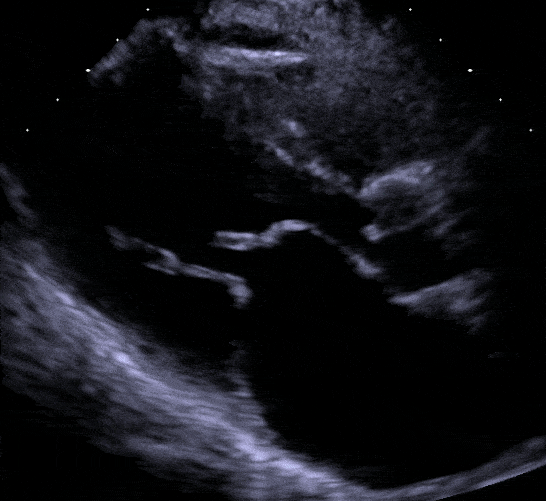

Apical twochamber view Showing a hockey stick appearance Hockey Stick Sign Echo The mitral leaflets were pliable, with restricted mobility of the. transthoracic echocardiography revealed findings typical of rheumatic mitral stenosis. echocardiography features of rheumatic mitral stenosis. Most = rheumatic heart disease. Anterior mitral leaflet has characteristic. (a) diastolic doming of the thickened anterior mitral valve. Hockey Stick Sign Echo.

Hockey Stick Sign Echo . transthoracic echocardiography revealed findings typical of rheumatic mitral stenosis. (a) diastolic doming of the thickened anterior mitral valve. Most = rheumatic heart disease. Anterior mitral leaflet has characteristic. echocardiography features of rheumatic mitral stenosis. The mitral leaflets were pliable, with restricted mobility of the.